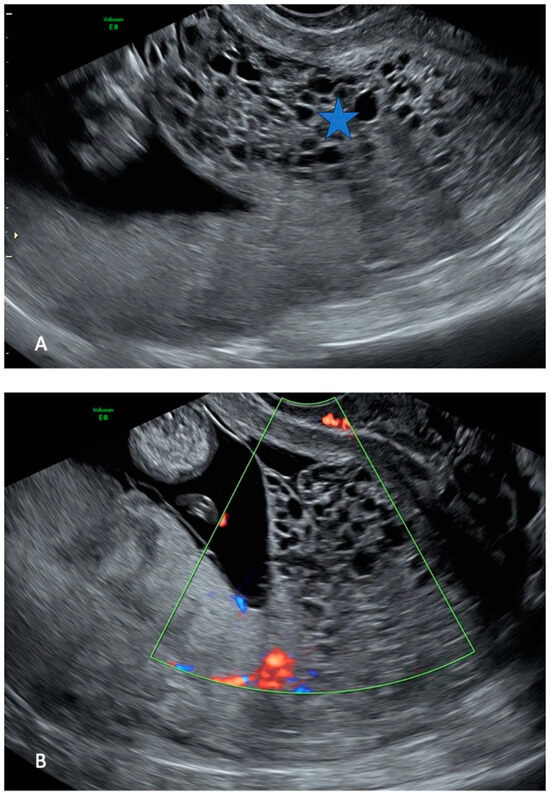

Histologically, the placenta showed a regular villous maturation for 38 weeks of gestational age. The hydropic component showed enlarged and vacuolated villi with well-formed cisterns. The villous trophoblast was circumferentially hyperplastic with atypia involving both cytotrophoblasts and syncytiotrophoblasts (Figure 4). Immunohistochemistry for p57KIP2 was negative in the hydropic component (Figure 5), indicating a CHMCF.

Figure 4.

(A): Histological findings of coexisting normal pregnancy with hydatiform complete mole: normal placental villi (left side of the image) concurred with villous hydropic degeneration (right bottom side of the picture). There was a sharp passage between normal villi and molar degeneration (hematoxylin and eosin 2HPF). (B): The molar component showed enlarged villi with formation of cisterns (star) (hematoxylin and eosin 4HPF). (C): The trophoblast was circumferentially hyperplastic with atypia (arrow) (hematoxylin and eosin 10HPF).

In the case we described, US detection of CHMCF was made early in gestation, at 13 weeks. Placental examination confirmed the US diagnosis, both grossly and microscopically. The enlarged, hydropic villi were adjacent to a normal placenta. Histologically, the typical cisterns with circumferential trophoblast hyperplasia were seen and immunohistochemistry for p57KIP2 was negative in the cytotrophoblast and stromal cells.